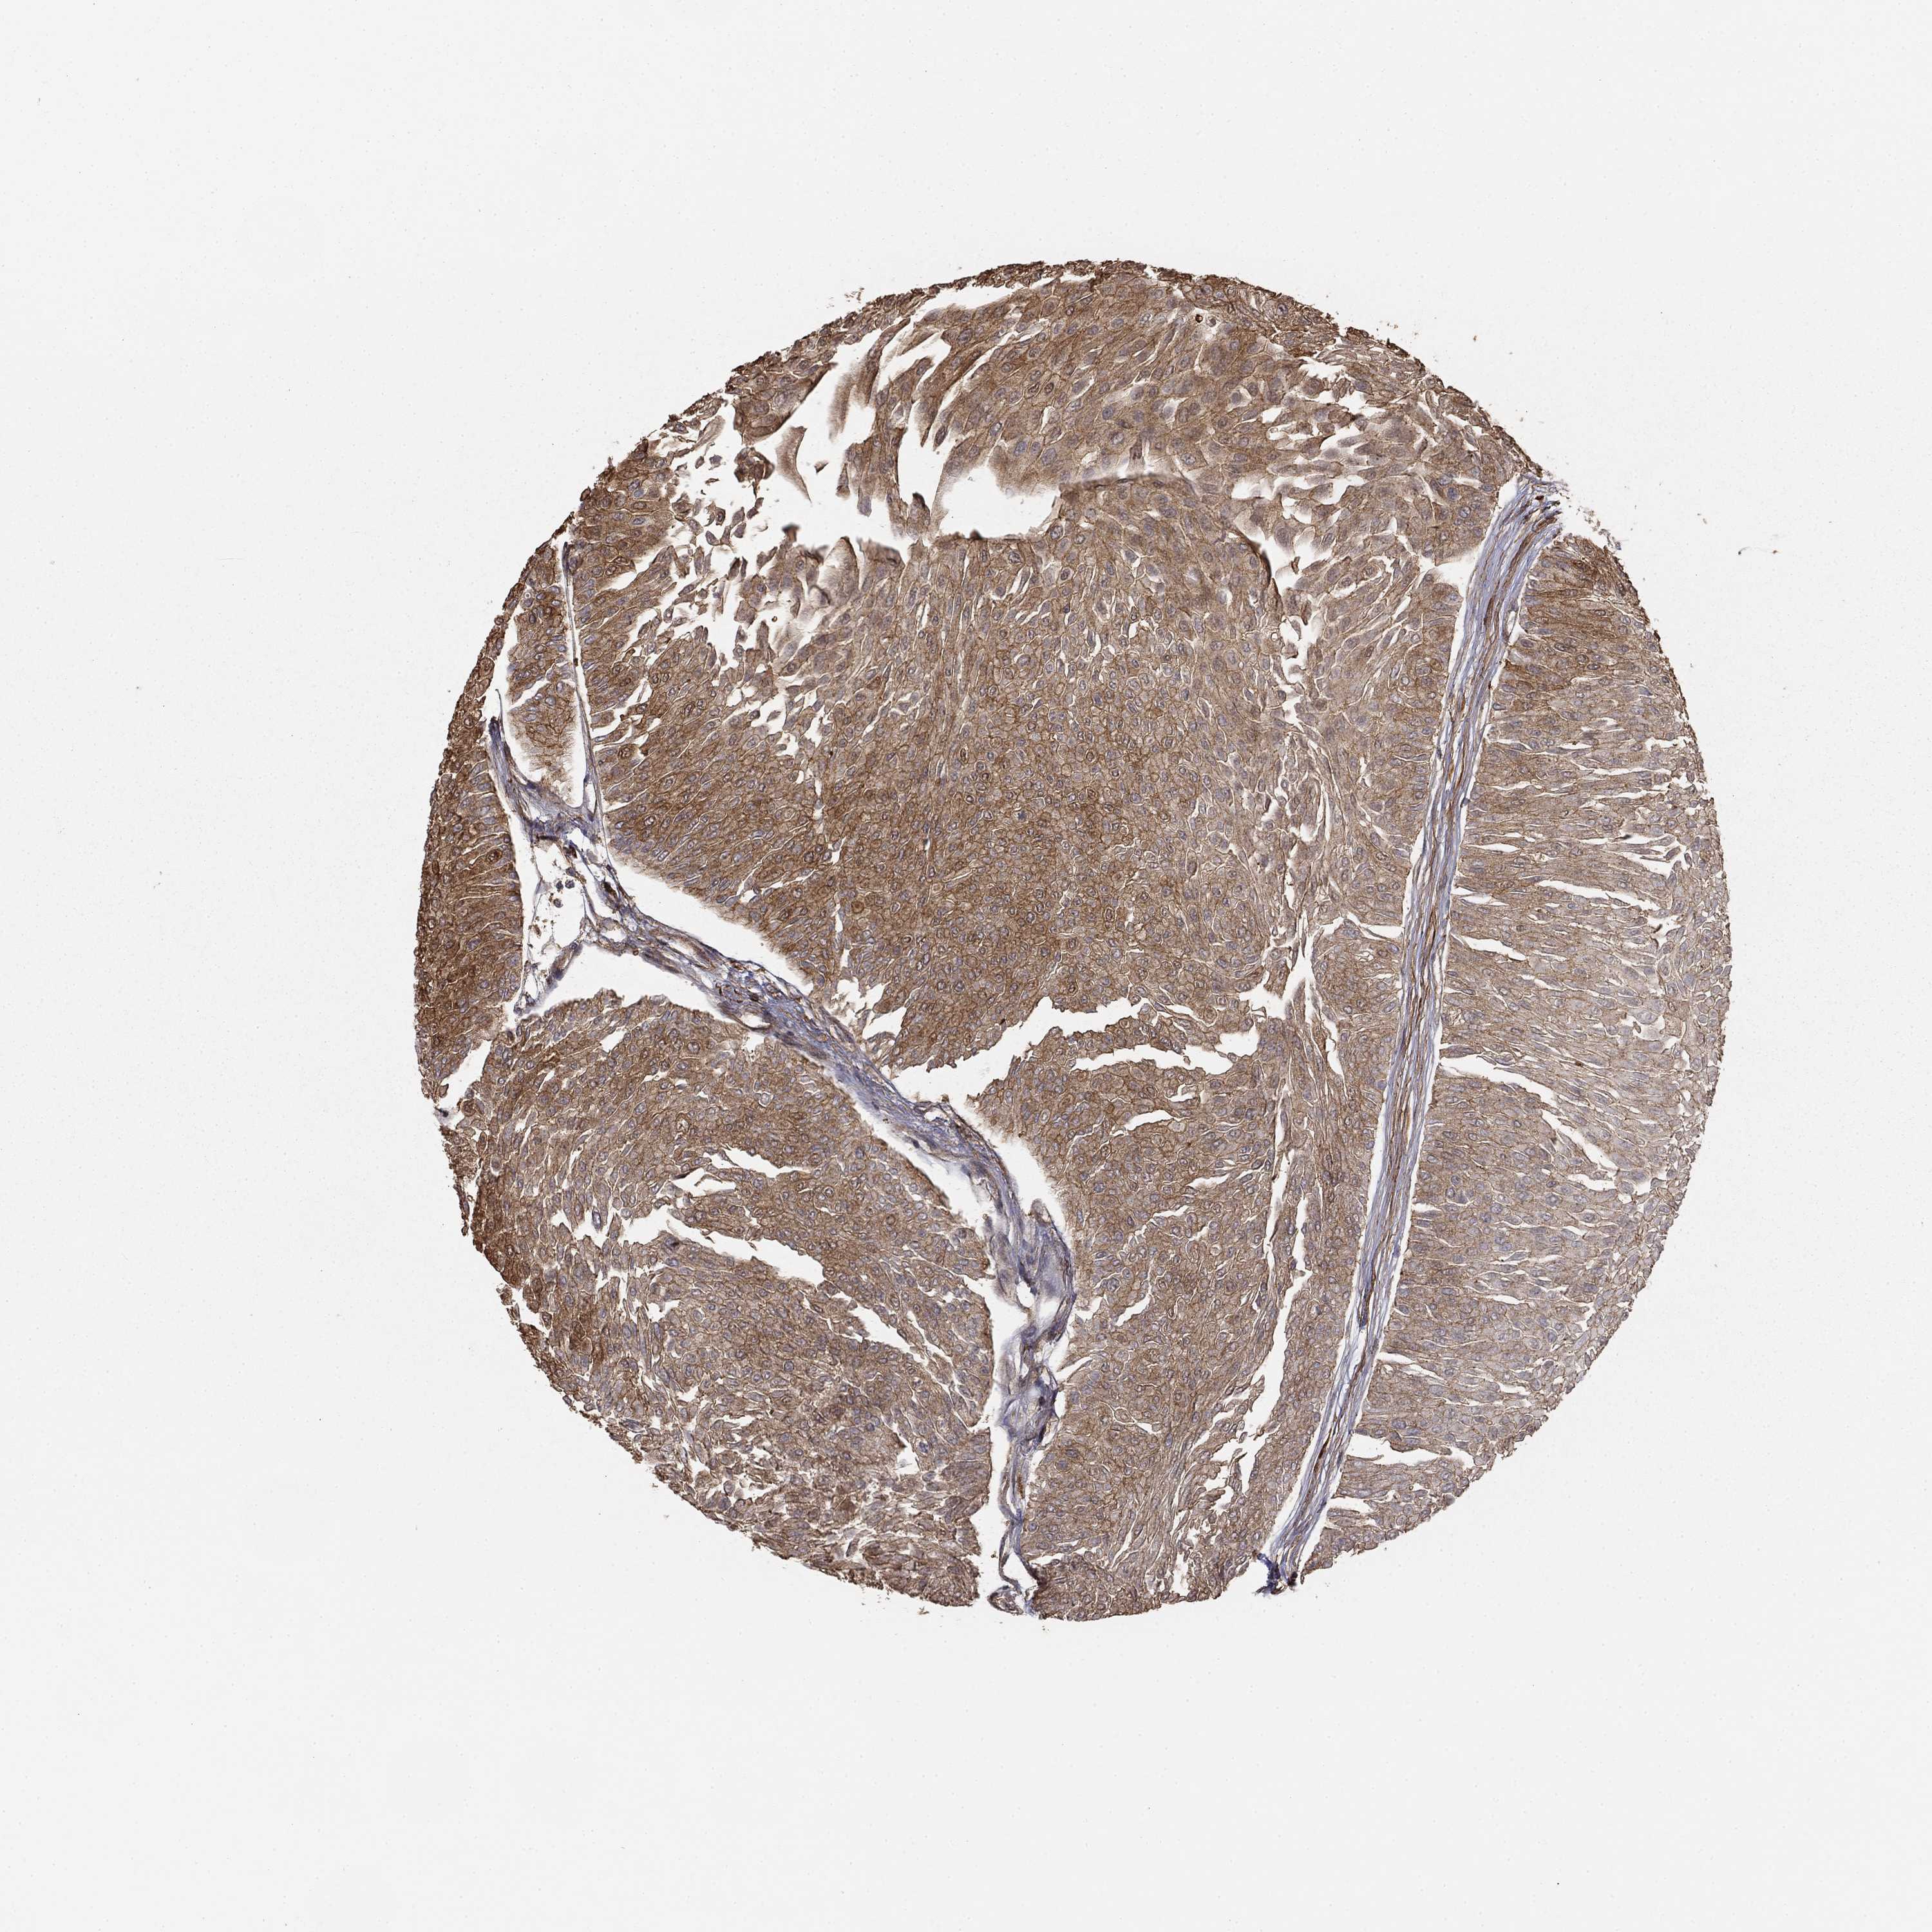

UROTHELIAL CANCER - Protein expressioni

A mouse-over function shows sample information and annotation data. Click on an image to view it in a full screen mode. Samples can be filtered based on level of antibody staining by selecting one or several of the following categories: high, medium, low and not detected. The assay and annotation is described here.

Note that samples used for immunohistochemistry by the Human Protein Atlas do not correspond to samples in the TCGA dataset.

Antibody stainingi

Antibody staining in the annotated cell types in the current human tissue is reported as not detected, low, medium, or high, based on conventional immunohistochemistry profiling in selected tissues. This score is based on the combination of the staining intensity and fraction of stained cells.

Each image is clickable and will lead to virtual microscopy that enables deeper exploration of all samples and also displays staining intensity scores, fraction scores and subcellular localization as well as patient and tissue information for each sample.

Antibody HPA055969

Antibody HPA062366

Staining

High

Medium

Low

Not detected

Intensity

Strong

Moderate

Weak

Negative

Quantity

>75%

75%-25%

<25%

None

Location

Nuclear

Cytoplasmic/membranous

Cytoplasmic/membranous,nuclear

Urothelial carcinoma, High grade

Urothelial carcinoma, NOS

Urothelial carcinoma, Low grade